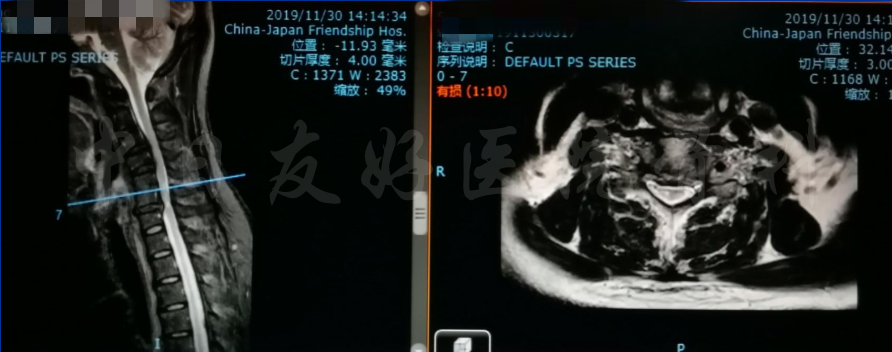

2019年11月30日 颈椎MRI提示:颈3/4颈4/5颈6/7椎间盘突出,椎管狭窄;颈5-6水平脊髓异常信号,变性可能。

颈椎MRI

颈椎各节段MRI(上下滑动)

腰椎MRI